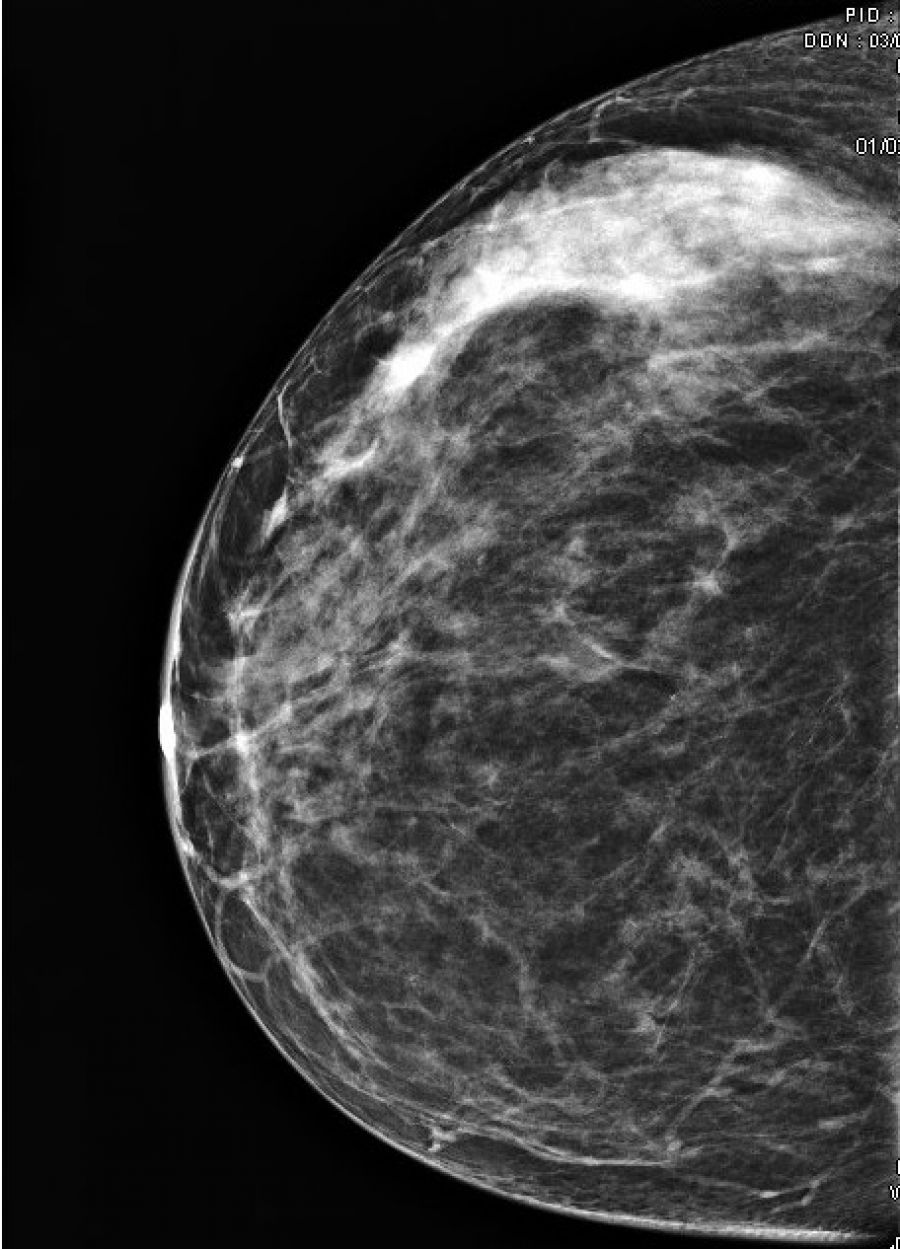

La tomosynthèse , c'est quoi ?

L’examen comporte 2 ou 3 clichés sur chaque sein. La compression du sein est nécessaire pour améliorer la qualité des clichés, donc l'efficacité du diagnostic radiologique. La compression est un peu désagréable. Elle est très rarement douloureuse. Si c'est le cas, la manipulatrice cessera immédiatement la compression.

• Ce premier bilan pourra être complété par d'autres clichés ou par une échographie pour être plus précis sur certains diagnostics.